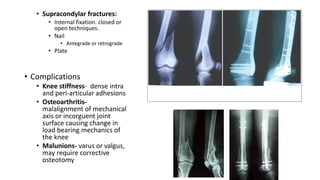

• Supracondylar fractures:

• Internal fixation. closed or

open techniques.

• Nail

• Antegrade or retrograde

• Plate

• Complications

• Knee stiffness- dense intra

and peri-articular adhesions

• Osteoarthritis-

malalignment of mechanical

axis or incorguent joint

surface causing change in

load bearing mechanics of

the knee

• Malunions- varus or valgus,

may require corrective

osteotomy